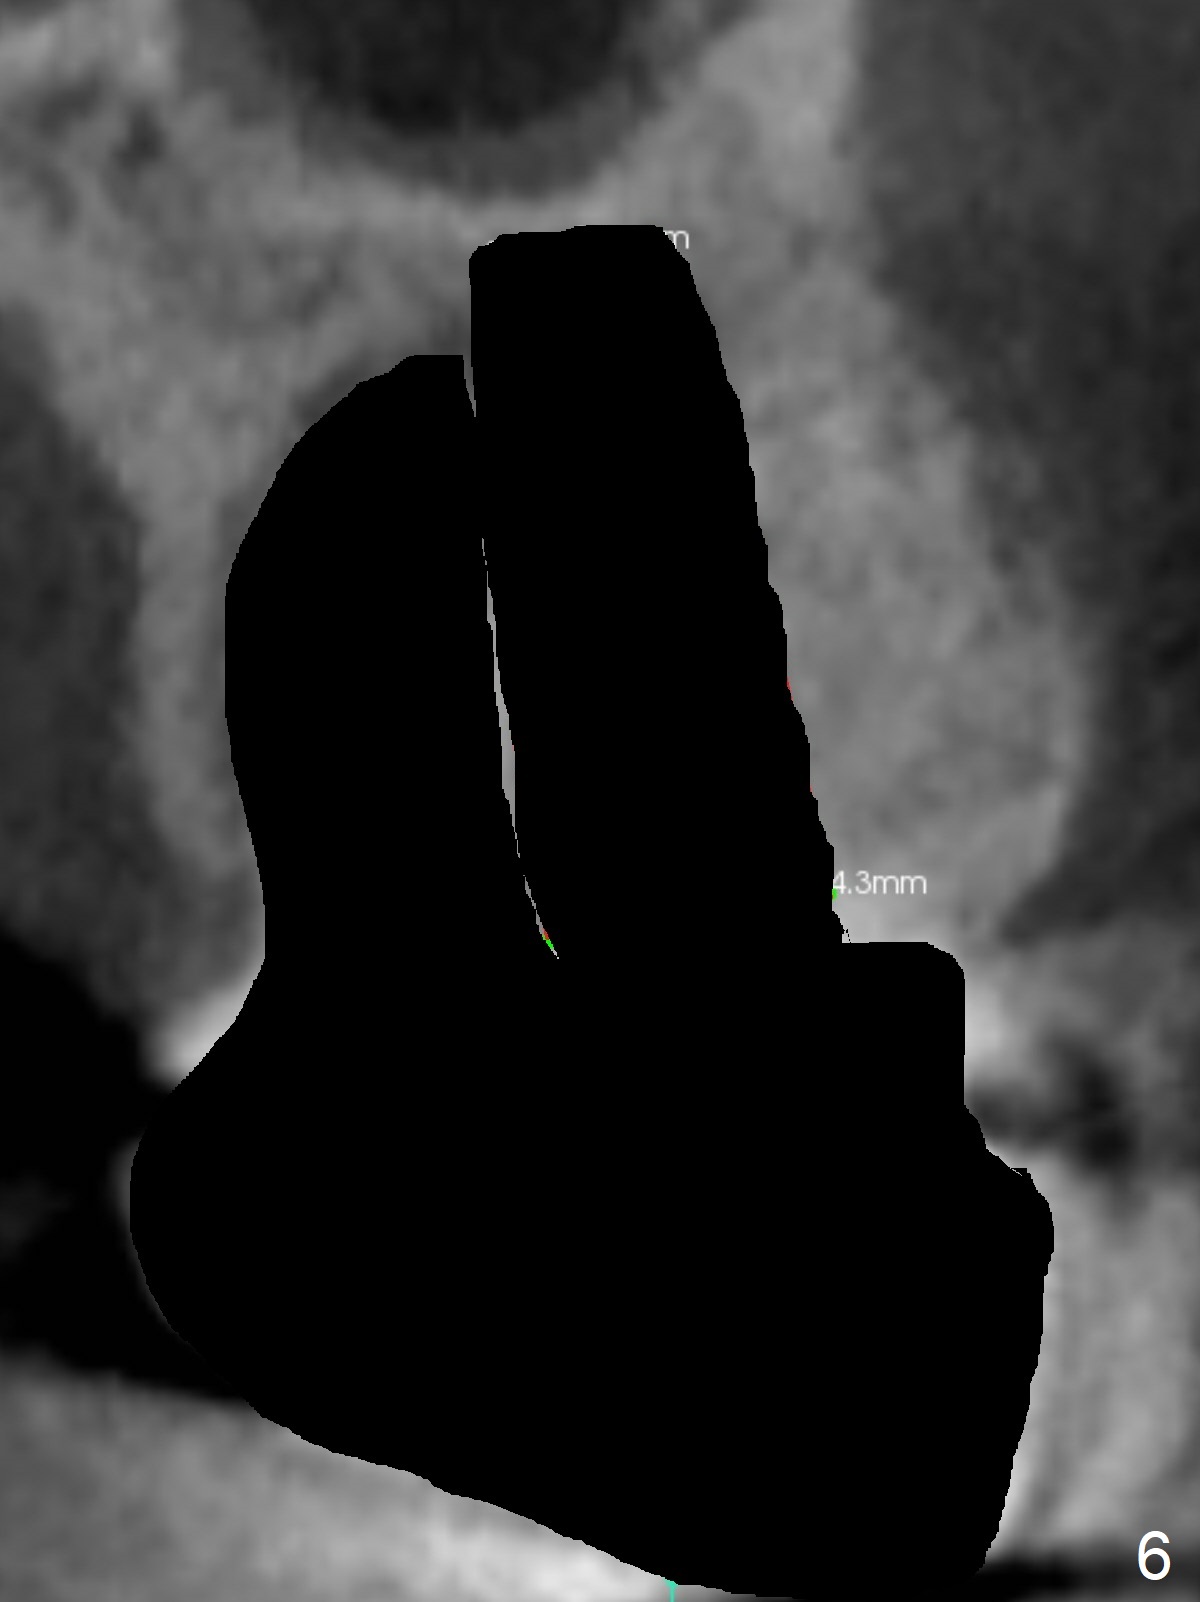

A 53-year-old man cannot chew on the left side with distal abscess in spite of RCT for #14 (* in Fig.1,2 (taken 11 ad 21 months postop, respectively)). After extraction (Fig.3 (CBCT coronal section) black area), start osteotomy with 2 mm drill (red outline) in the septum buccal to the palatal (P) socket). Following 2 mm drill removal (Fig.4), use 4.3 mm Magic Drill (red outline) for ~ 9 mm. When the osteotomy is being done, the osteotomy most likely shifts palatal (Fig.5 arrow) because of thin bone palatally. When the MD is removed (Fig.6), use Magic Sinus Lifter (Fig.7 pink) for sinus lift (arrow). The implant is to be 5x11 mm or larger. Because of the distal defect (Fig.1,2), start osteotomy mesially. Take Alginate impression before surgery for possible orthodontic treatment. Since bone density is high, use higher voltage and longer time for X-ray.